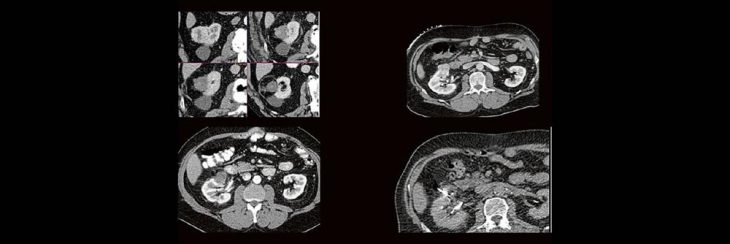

Professor Dr. med. Marc Brockmann WEITERENTWICKLUNGEN VON KOPF BIS FUSS BEIM VC Oberstarzt Dr. med. Stephan Waldeck DEEP-LEARNING-REKONSTRUKTION IN DER NEURORADIOLOGIE Die CT ist ein essentielles Routine-Verfahren in der Neuroradiologie. Bei steigender Bildqualität konnte die Röntgendosis mit neuen Technologien in der letzten Dekade deutlich gesenkt werden, was für die zielgerichtete und möglichst schonende Behandlung vonRead more about DEEP-Learning-Rekonstruktion in der Neuroradiologie (Webinar | Online)[…]